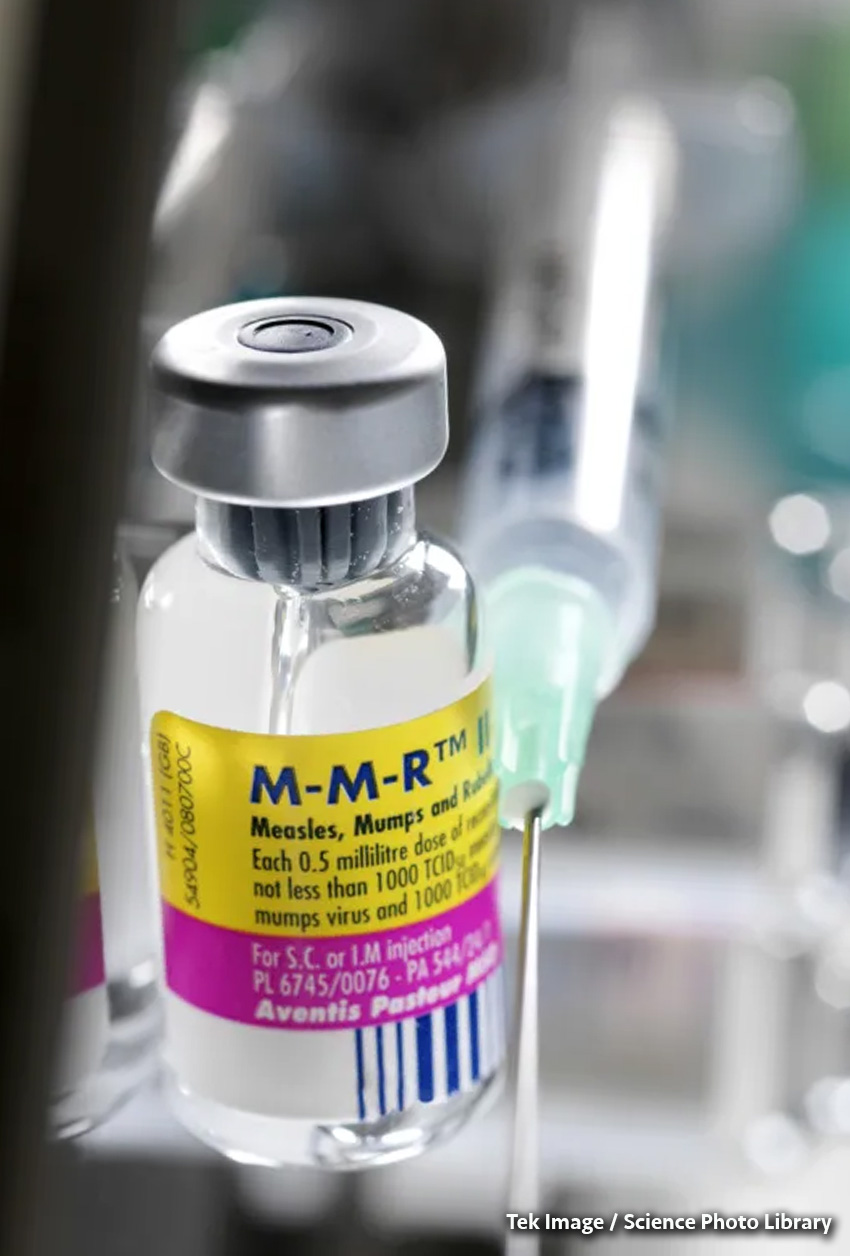

La OMS, «extremadamente preocupada» por el creciente escepticismo sobre la vacunación

Según la Organización Mundial de la Salud (OMS), el escepticismo sobre la vacunación y el colapso de la financiación de las campañas de vacunación plantean una gran amenaza para la salud de la población mundial. “Estamos sumamente preocupados por la desinformación y la información errónea sobre ... Leer Más